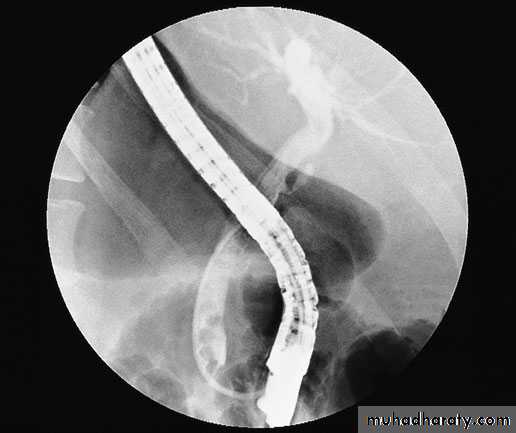

36ERCP is required in patients with obstructive jaundice who cannot undergo MRCP because of claustrophobia

or where an endoscopic intervention is anticipated based on previous imaging [endoscopic removal of common bile duct (CBD) stones or insertion of a palliative biliary tract stent].

Endoscopic retrogradecholangiopancreatography

38A preoperative check of coagulation is essential, along with prophylactic antibiotics and an explanation of the main complications, which include pancreatitis, cholangitis and bleeding or perforation of the duodenum related to sphincterotomy.